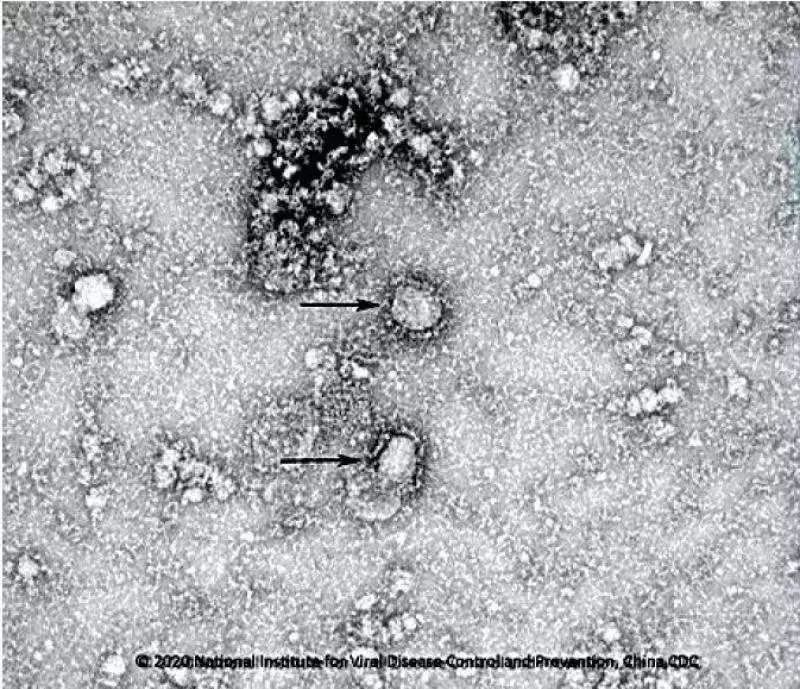

据香港《东方日报》2月1日报道称,香港大学病理学系临床医学教授黎国思(John Nicholls)与香港大学医学院公共卫生学院教授潘烈文和裴伟士(MalikPeiris)通过培养受感染细胞,观察新型冠状病毒的生长过程。

新型冠状病毒的薄片电子显微图像显示,病毒粒子从受感染细胞的表面释放出来。

黎国思表示,每个受感染的细胞会衍生出数以千计的病毒粒子,从而继续感染新细胞。

研究人员还研究了病毒在不同生长时间的样本,以便更清楚地了解病毒的复制过程,并与其他冠状病毒进行了比较。